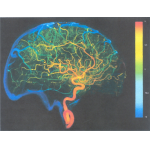

Digital Subtraction Angiography (DSA)

Digital Subtraction Angiography (DSA) awalnya adalah teknik yang dilakukan untuk menggambar pembuluh darah, dengan menyemprotkan zat kontras (iodine) agar bisa dideteksi oleh alat X-ray melalui film. DSA bisa diaplikasikan pada pembuluhjantung, ke...